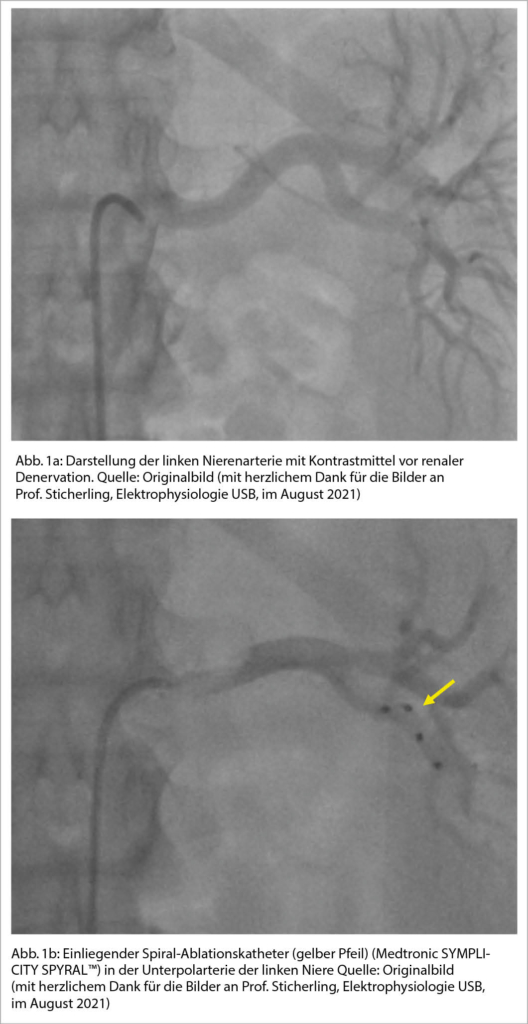

Als mögliche Ursachen der neutralen Ergebnisse wurden neben einer zum Teil begrenzten Erfahrung der Interventionalisten auch technische und anatomische Besonderheiten angegeben. So hat das Scheitern von Symplicity HTN-3 ein erneutes Interesse an der Anatomie und Physiologie der renalen Nervenfasern geweckt, und man konnte lernen, dass der Abstand des Nervengeflechts zum Gefässlumen von proximal nach distal abnimmt. Somit erscheint eine distalere Energieabgabe bis in einzelne Polarterien sinnvoller (Abb. 1), was jedoch konträr zur initialen Interventionstechnik ist, bei der empfohlen wurde eher proximal die Energie zu applizieren. Insgesamt ergab sich in den letzten Jahren eine Entwicklung hin zu ausgefeilteren Katheterdesigns und die Behandlungsalgorithmen wurden angepasst, um eine vollständigere und zuverlässigere RDN zu erreichen.